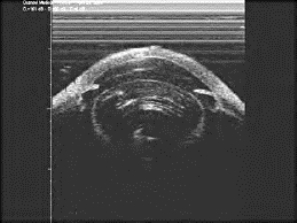

图19-1 晶状体膨隆

②膨胀期或未成熟期(intumescent stage or immature stage):晶状体混浊继续加重,原有的楔形混浊向瞳孔区发展并互相融合,视力显著下降。由于渗透压改变,晶状体吸收水分,体积膨胀、增大,导致前房变浅(图19-1),少数病人可以诱发急性青光眼,此时可见空泡、水裂和板层分离。因晶体前囊下仍有透明皮质,斜照法检查可见虹膜投影。患者视力明显下降,眼底难以观察。